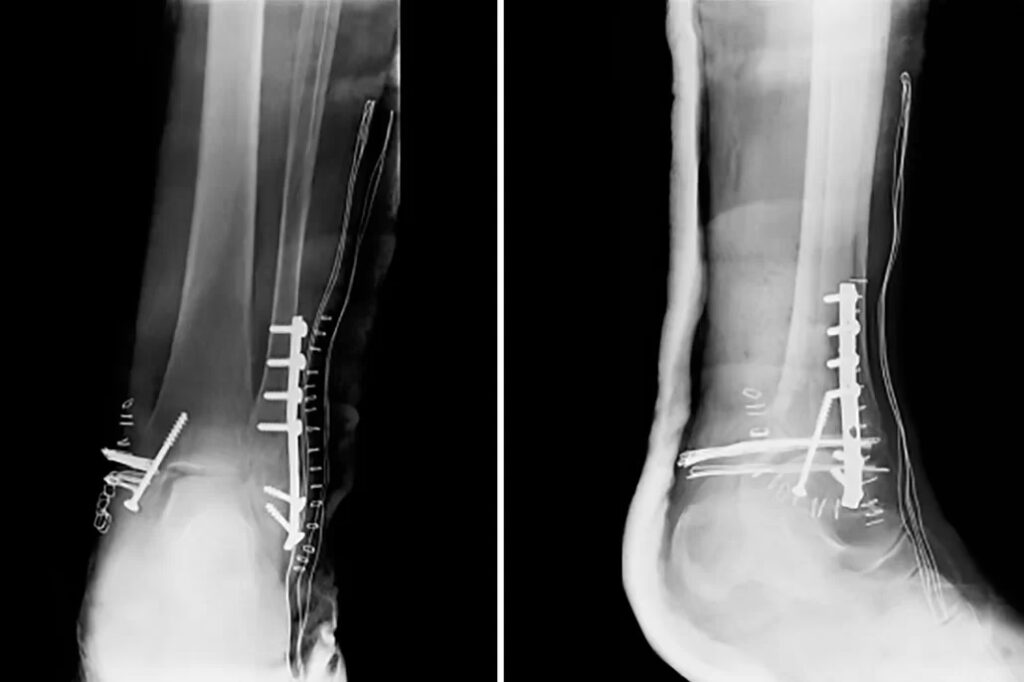

Aunque el enfoque principal es la fractura de la diáfisis (parte larga) de la tibia y el peroné, es relevante mencionar las fracturas que afectan el extremo distal de estos huesos, formando la articulación del tobillo. Una fractura trimaleolar, por ejemplo, es una fractura compleja que involucra el maléolo medial (parte interna de la tibia en el tobillo), el maléolo lateral (extremo distal del peroné) y el maléolo posterior (parte trasera del extremo distal de la tibia).

Estas fracturas trimaleolares suelen estar desplazadas y requieren cirugía para restaurar la alineación anatómica de la articulación del tobillo. Un diagnóstico y tratamiento precoz son de vital importancia para la evolución futura de estas lesiones. Como se ha visto en la práctica clínica, realizar una cirugía sobre el tobillo después de transcurridas las dos primeras semanas del trauma inicial se torna más difícil debido a la inflamación y la retracción de tejidos.

Un caso reportado ilustra la complejidad del tratamiento de una fractura trimaleolar diagnosticada y tratada quirúrgicamente seis semanas después de la lesión. Aunque el paciente, un hombre joven, logró una recuperación funcional con rangos de movimiento normales y sin dolor a los seis meses post-cirugía, el abordaje quirúrgico fue más complejo debido al retraso. Esto subraya que el tiempo transcurrido desde la lesión hasta el tratamiento puede influir en la complejidad de la cirugía y, potencialmente, en el camino hacia la recuperación, aunque un resultado favorable es posible con atención especializada.